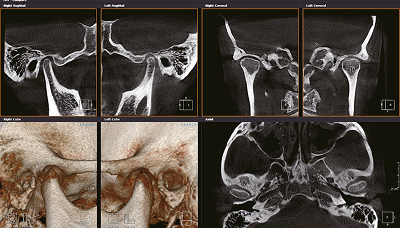

Челюстно-лицевая хирургия

Снимки левого и правого ВНЧС единым снимком. Изображения ВНЧС размером 200 мкм помогают произвести максимально качественную диагностику ВНЧС.